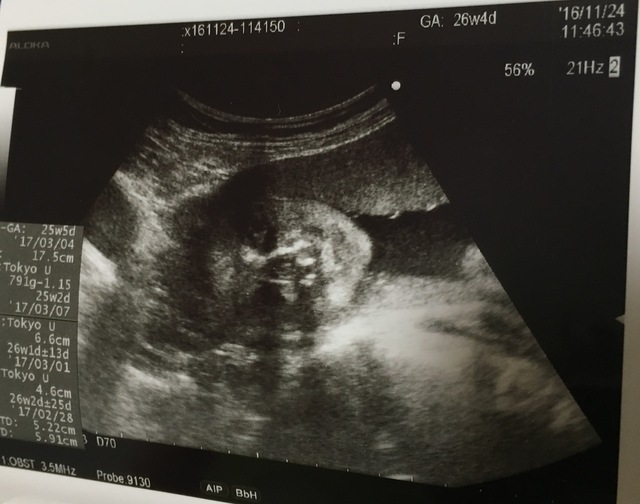

25週0日(25w0d・男の子)|ち75 さん(32歳)

エコー写真撮影時のエピソード:

昔にバンドのボーカルをやっていたり、歌うことも音楽を聴くことも好きなので、妊娠中は今まで行こうと思って行けなかったバンドのライブに行く事にしました。

ライブ中も胎動が激しい曲や何も動かない曲など、好みがあるみたいで面白かったです。エコー写真は歌っている様に、口をパクパクしていた時の息子です。